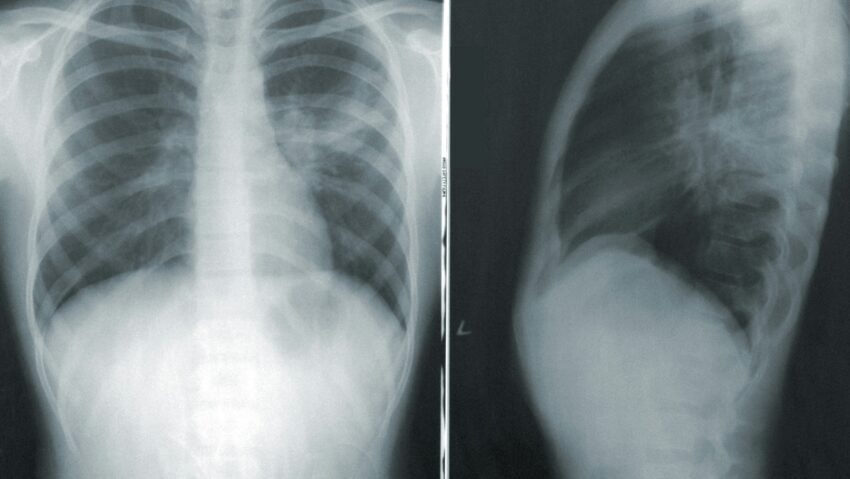

A tuberkulózis, azaz a TBC, a múlt évben 1 230 000  áldozatot követelt és ezzel globális szinten az első számú halálos fertőző megbetegedésnek számít – áll az Egészségügyi Világszervezet szerdai közleményében. Becslések szerint 2024-ben világszerte 10 700 000 ember fertőződött meg tuberkulózissal, amely elleni küzdelem finanszírozása 2020 óta nem változott. Tavaly világszinten 5,9 milliárd dollár állt rendelkezésre megelőzésre, diagnosztizálásra és kezelésre – ez jóval elmarad a 2027-ig évente szükségesnek becsült 22 milliárd dolláros összegtől – írja a közlemény.

Romániában hosszú ideig tendencia volt az esetek számbeli csökkenése, de az utóbbi két-három évben ez a csökkenés megállt – hívta fel a figyelmet rádióknak Dr. Szőcs Ottó háziorvos. A szakember kiemelte, hogy a tuberkulózis mindig is a társadalom peremén élők betegsége volt, és a velük való együttműködés mai napig nehézséget jelent; éppen ezért az egészségügynek elsősorban abban kellene fejlődnie, hogy hatékonyabban integrálja őket a kezelésekbe – azonban egy ilyen feladatot ellátó külön ügyosztály létrehozása anyagi szempontból túl nagy terhet jelent az egészségügyi hatóságnak.